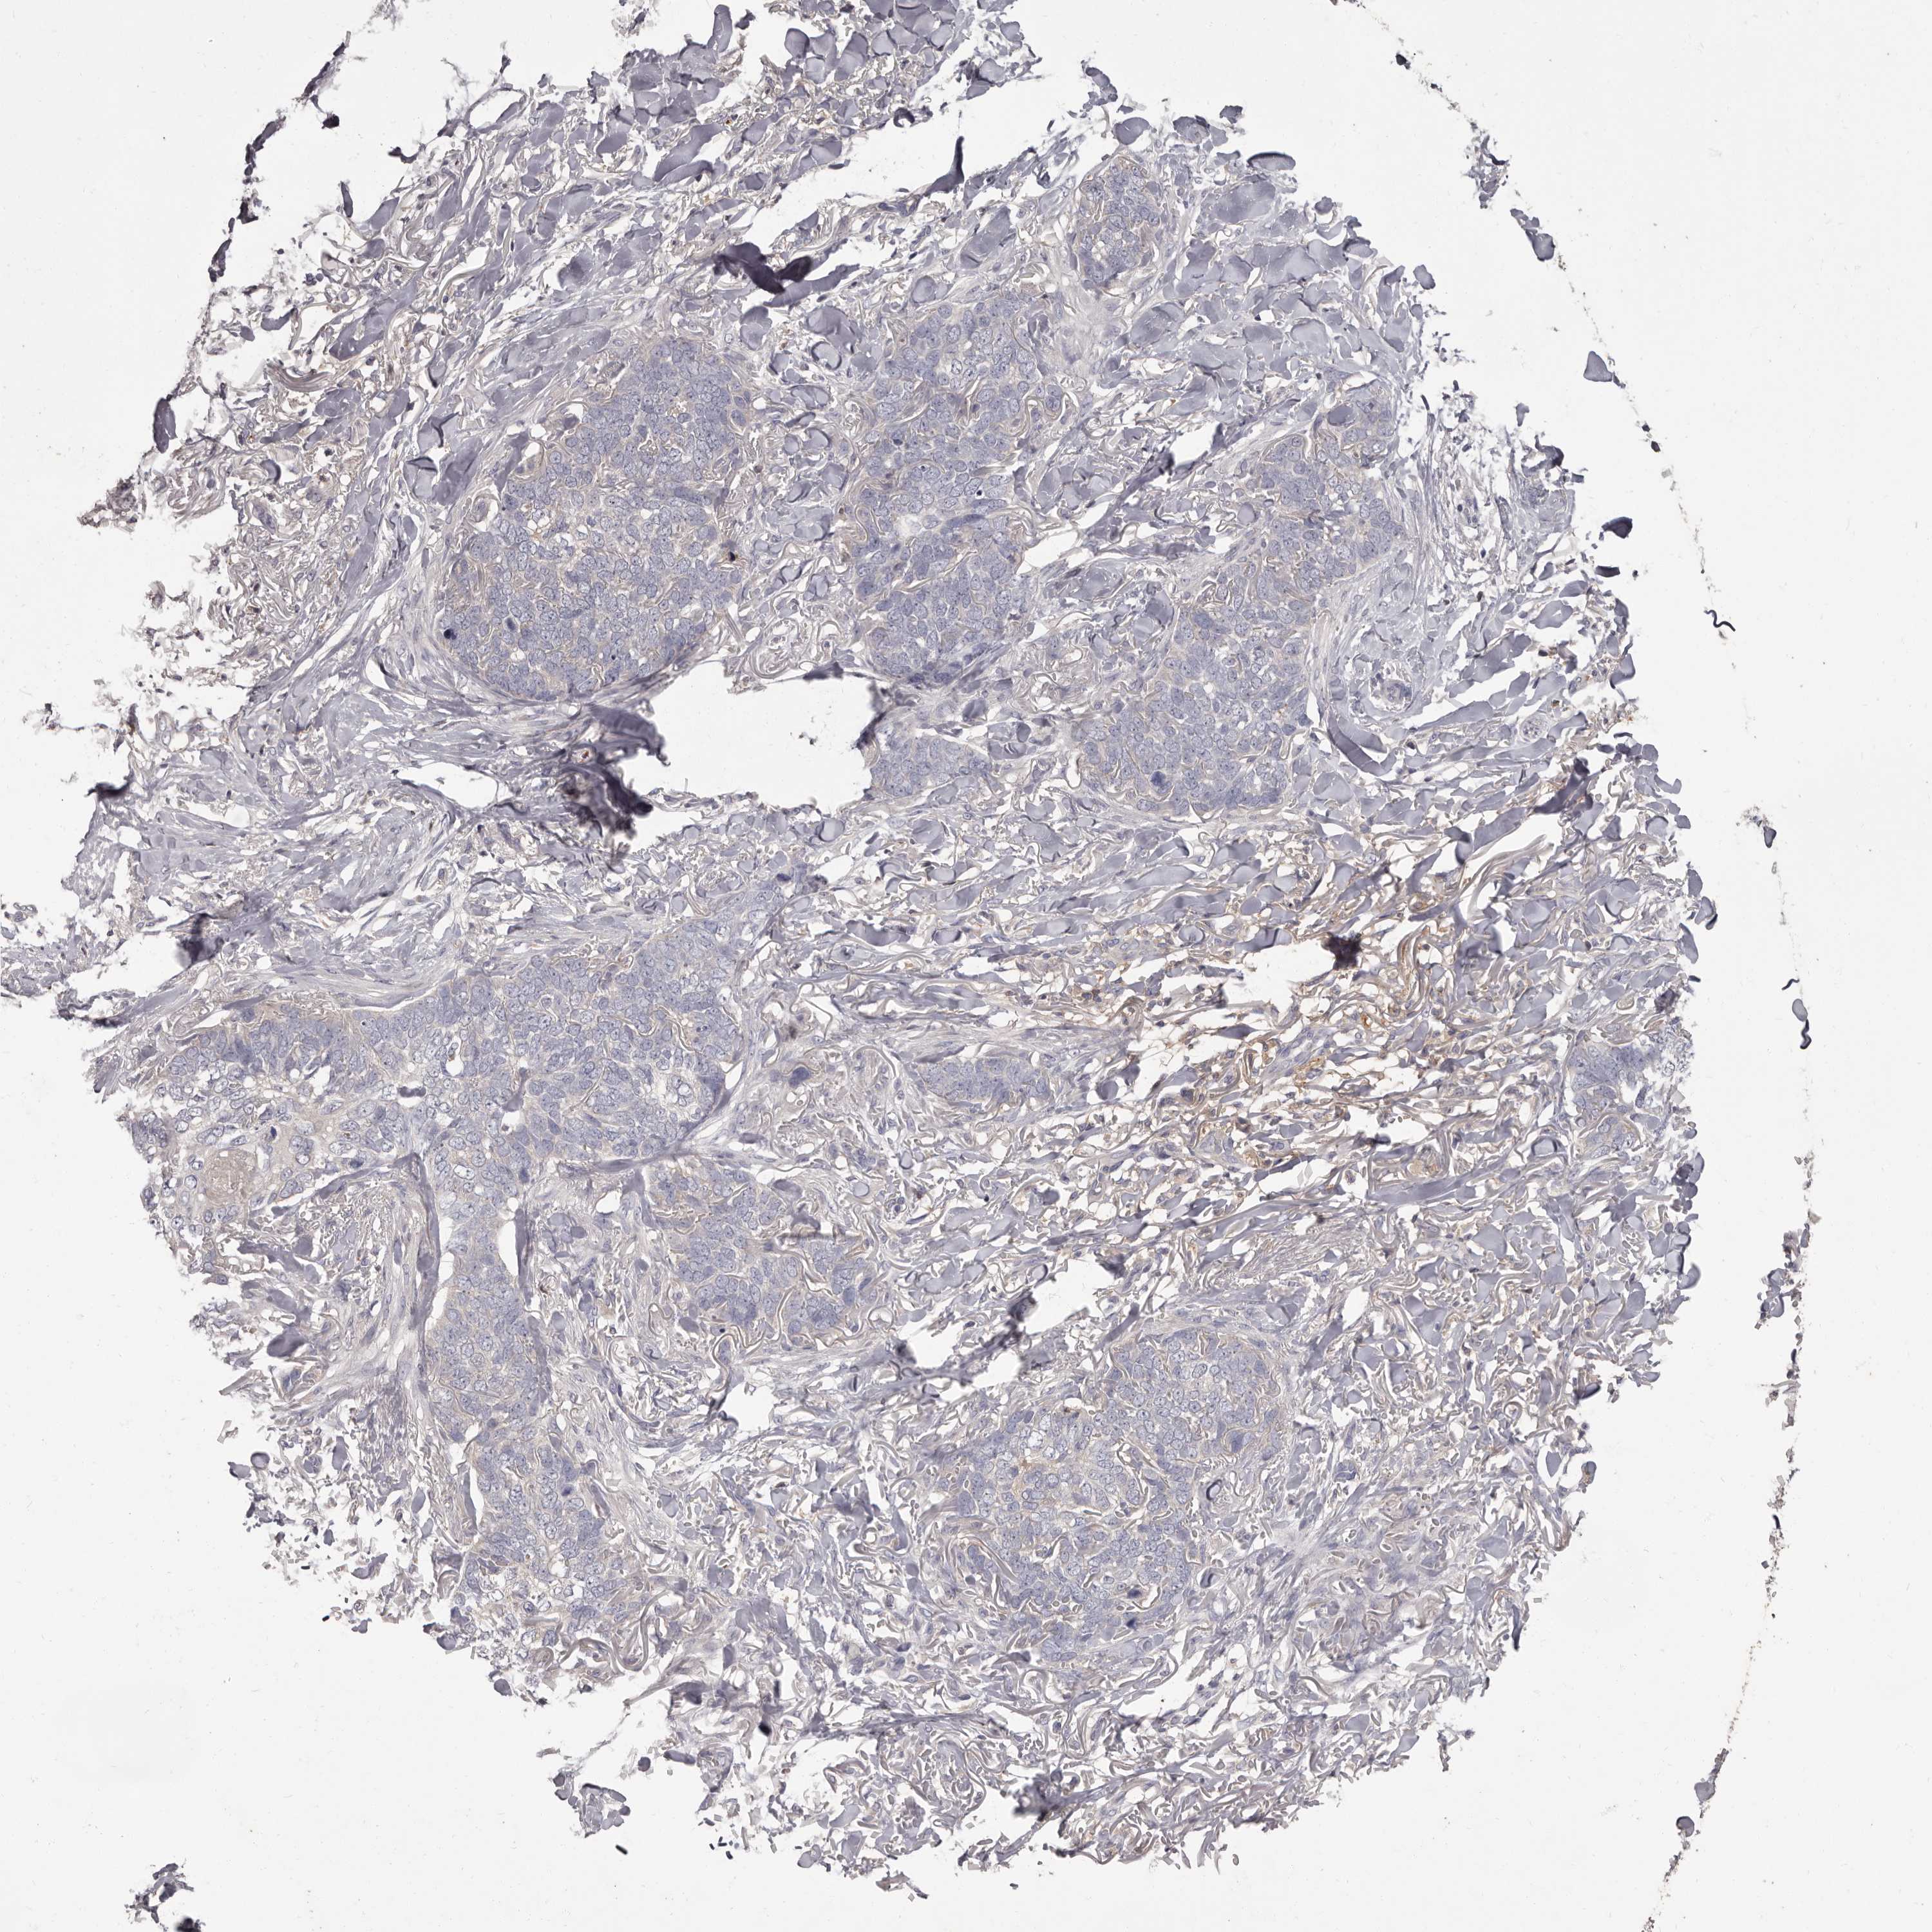

SKIN CANCER - Protein expressioni

A mouse-over function shows sample information and annotation data. Click on an image to view it in a full screen mode. Samples can be filtered based on level of antibody staining by selecting one or several of the following categories: high, medium, low and not detected. The assay and annotation is described here.

Antibody stainingi

Antibody staining in the annotated cell types in the current human tissue is reported as not detected, low, medium, or high, based on conventional immunohistochemistry profiling in selected tissues. This score is based on the combination of the staining intensity and fraction of stained cells.

Each image is clickable and will lead to virtual microscopy that enables deeper exploration of all samples and also displays staining intensity scores, fraction scores and subcellular localization as well as patient and tissue information for each sample.

Antibody HPA029700

Antibody HPA029701

Antibody HPA029702

Antibody HPA029703

Squamous cell carcinoma, metastatic, NOS